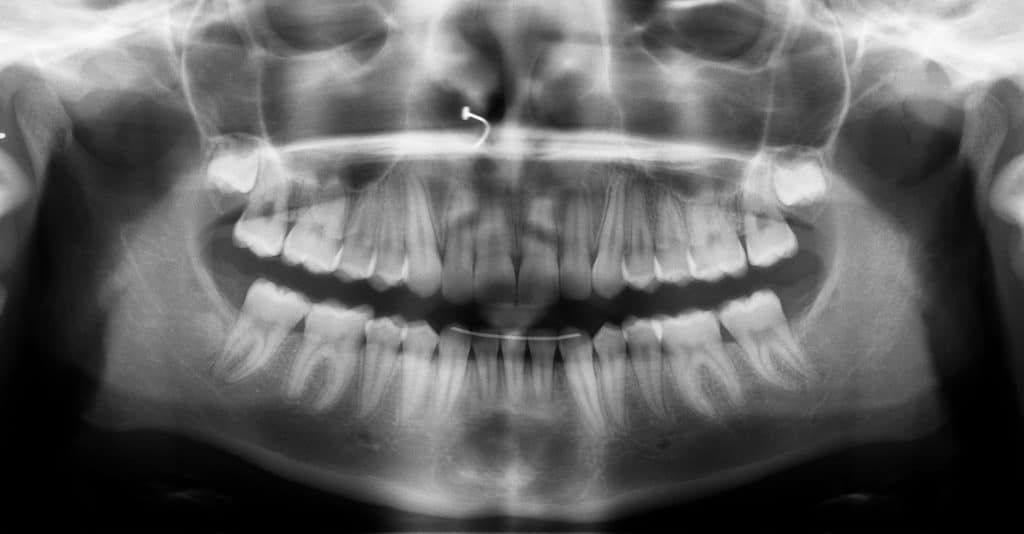

Una de las cosas más difíciles de conseguir es el paralelismo entre las raíces de los incisivos inferiores, en la radiografía siguiente se puede comprobar que las raíces esta perfectamente paralelas entre si al final del tratamiento.